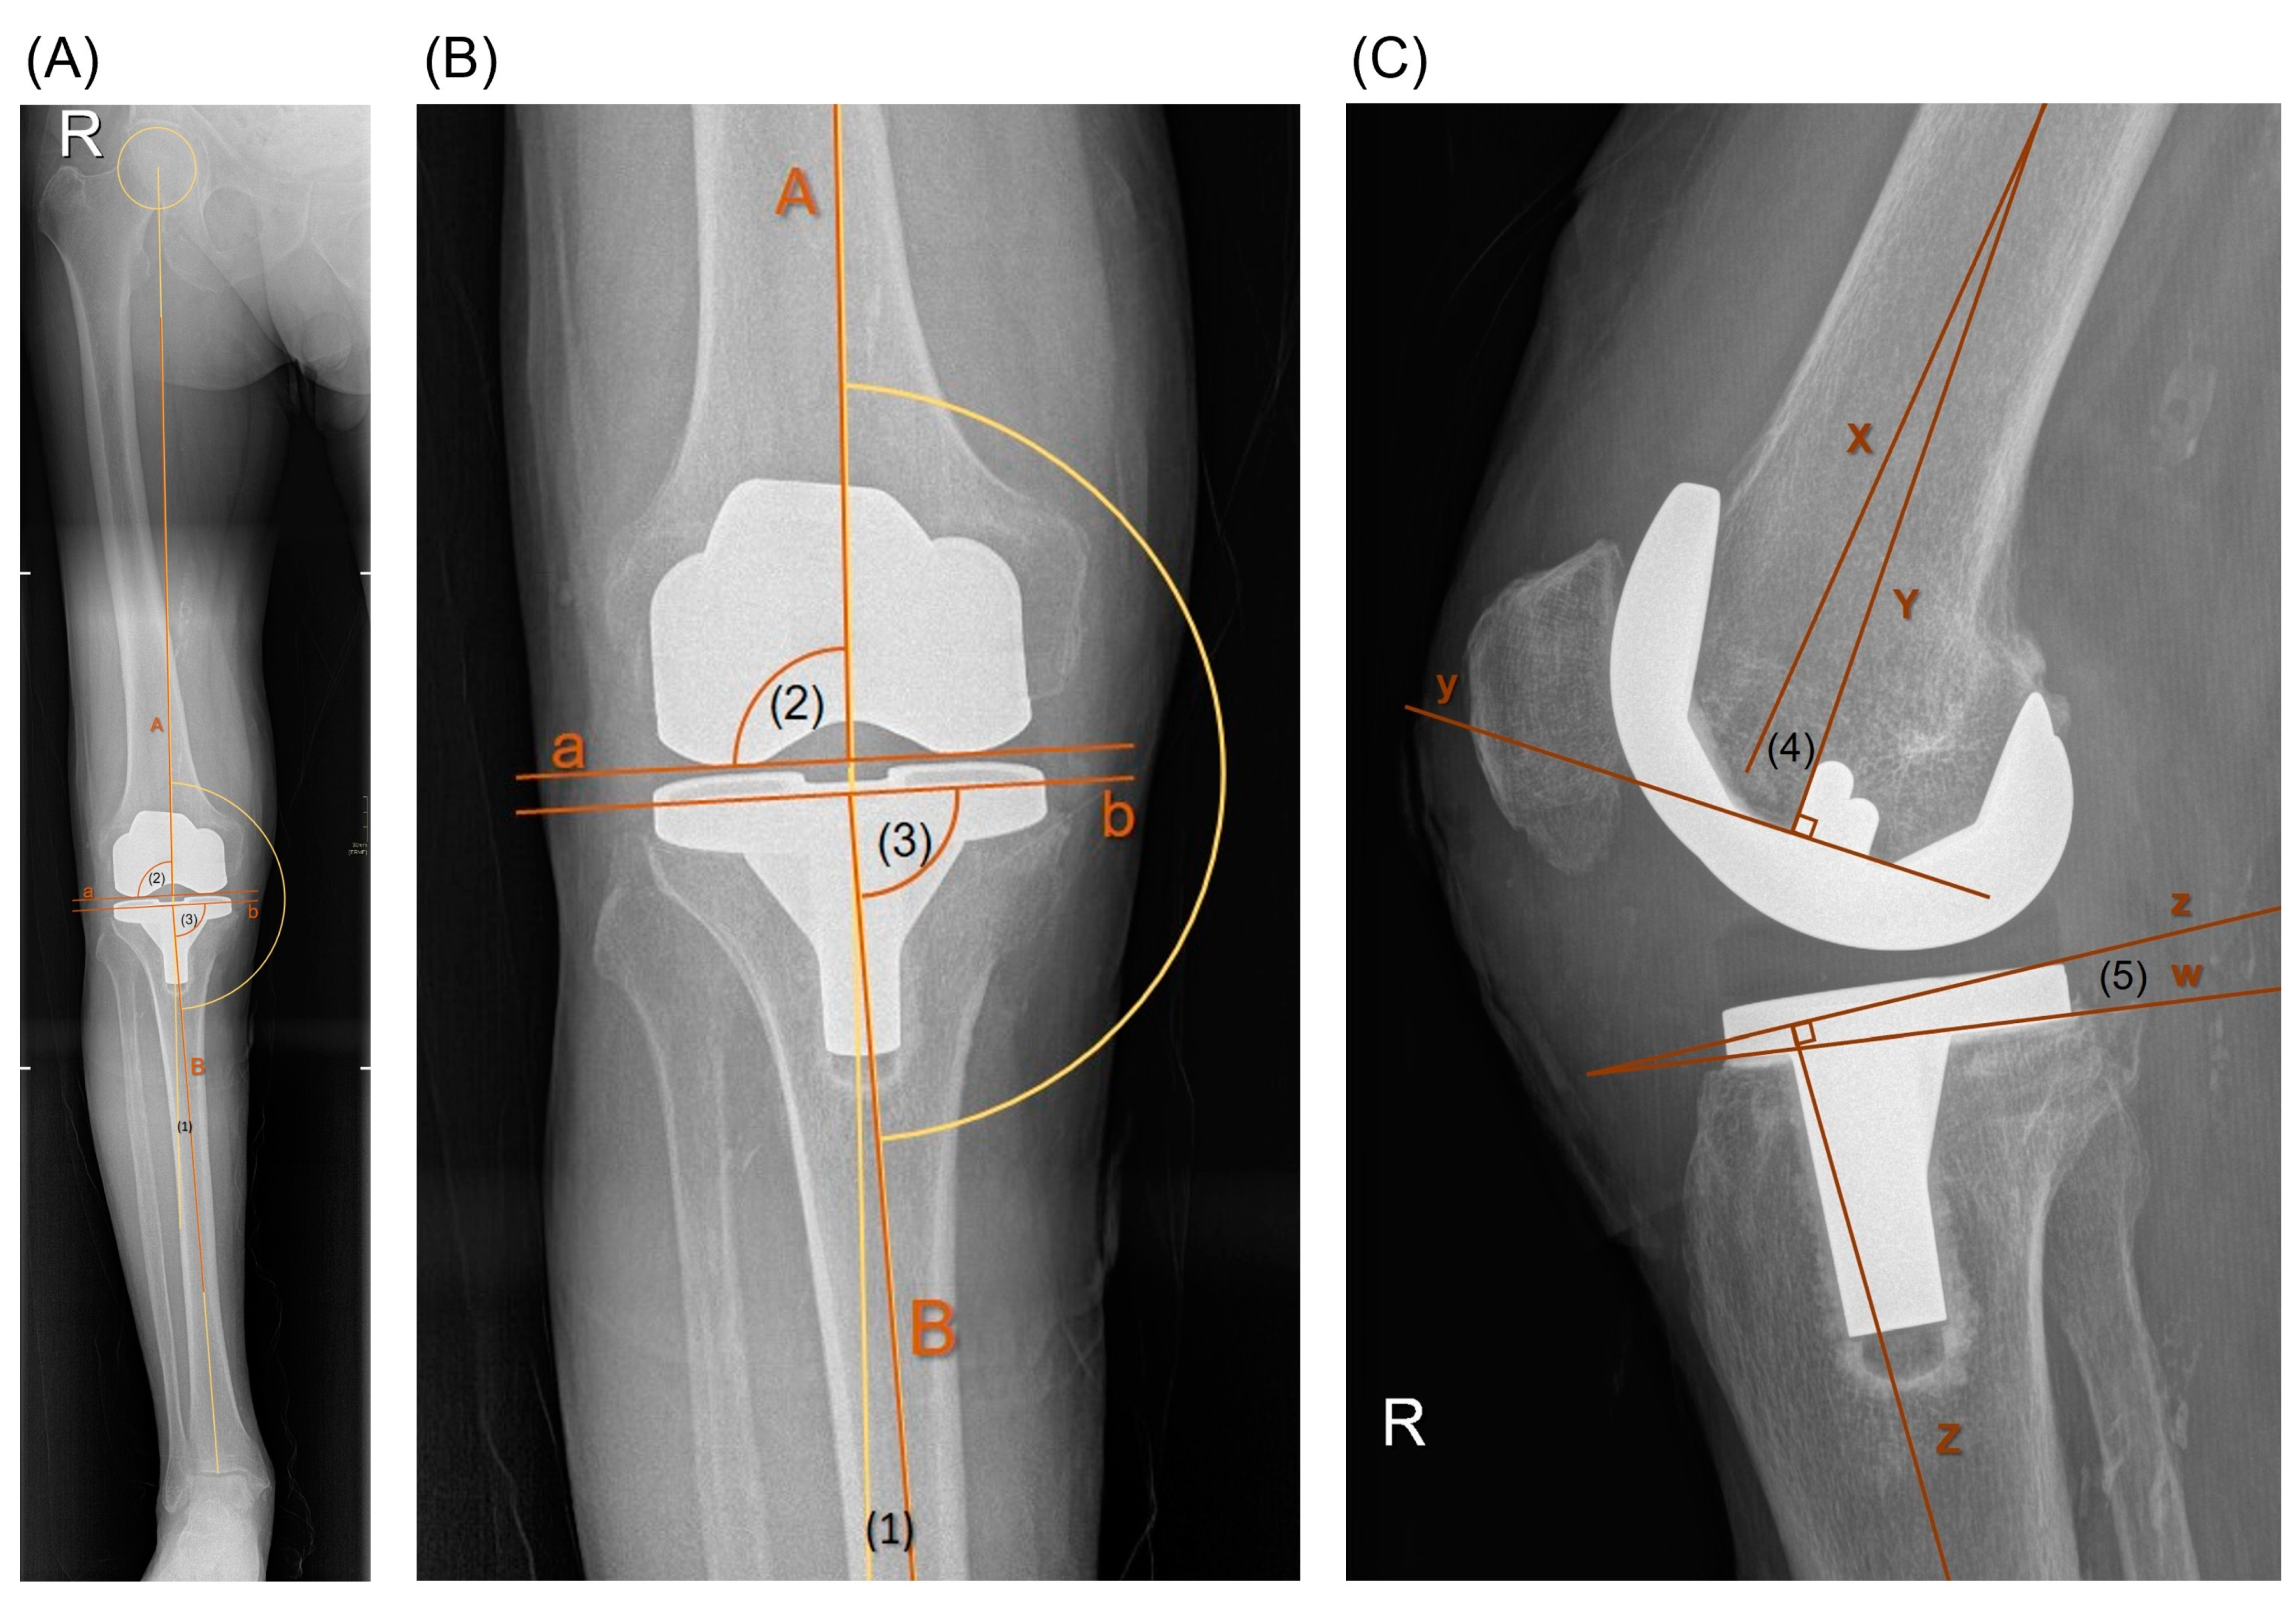

Radiological diagnostic studies were conducted using the Enterprise Imaging 8.2.0.140 software (AGFA HealthCare, 2640 Mortsel, Belgium) on long-leg standing anteroposterior (AP) and standard short film lateral knee view [37]. Alignment and component positioning were assessed based on HKAA, mLDFA, MPTA, DFFA, and TS (refer to Figure 4).

Figure 4. (A) Long-leg standing AP view. (B) Enlarged image (A): A = femoral mechanical axis; B = tibial mechanical axis; a = distal horizontal tangent to the femoral component; b = proximal horizontal tangent to the tibial component; (1) hip-knee-ankle (HKA) angle; (2) mechanical lateral distal femoral angle (mLDFA) = angle within [A] and [a]; (3) medial proximal tibial angle (MPTA) = angle within [B] and [b]. (C) Lateral knee view: X = femoral anatomical axis in sagittal plane; y = horizontal tangent to the femoral component; Y = perpendicular axis to [x]; (4) distal femoral flexion angle (DFFA) = angle within [X] and [Y]; Z = tibial anatomical axis in sagittal plane; z = perpendicular horizontal to Z; w = proximal tangent to the tibial component; (5) tibial slope (TS) = angle within [w] and [z].